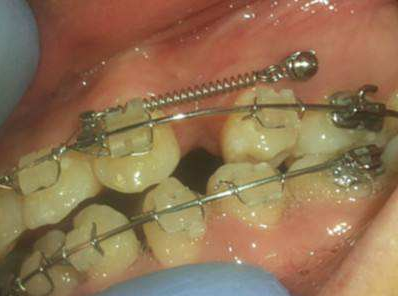

骨釘,顧名思義,是一種外形十分像釘子的種植釘,是放置在牙骨上方一個迷你的"釘子"。

它體積的小,好植入,近年來,逐漸成為正畸科常用的正畸輔助工具。

但是有了骨釘植入,就可以解決前者調(diào)節(jié)方案的煩惱,可以根據(jù)不同的調(diào)節(jié)方案,不同的調(diào)節(jié)需求,在口腔中相應(yīng)的位置植入骨釘形成口腔中的一個受力點(diǎn),同時利用正畸器,橡皮筋相互拉力的作用下,更好的幫助醫(yī)生更好的控制牙齒的移動,做到"該移動的牙移動,不該動的牙不動"從達(dá)到佳的調(diào)節(jié)果。